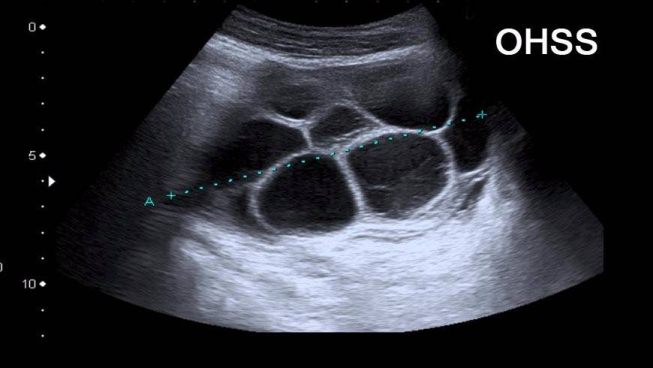

2- سونوگرافی

اگر OHSS داشته باشید، اولتراسوند ممکن است نشان دهد که تخمدان شما بزرگتر از حد معمول است و کیست های پر شده با مایع که در آن فولیکول ها رشد کرده اند، دیده شود. در طول درمان با داروهای باروری، دکتر به طور مرتب تخمدان را با سونوگرافی واژینال (سونوگرافی واژینال چگونه انجام می شود؟ ) بررسی می کند.